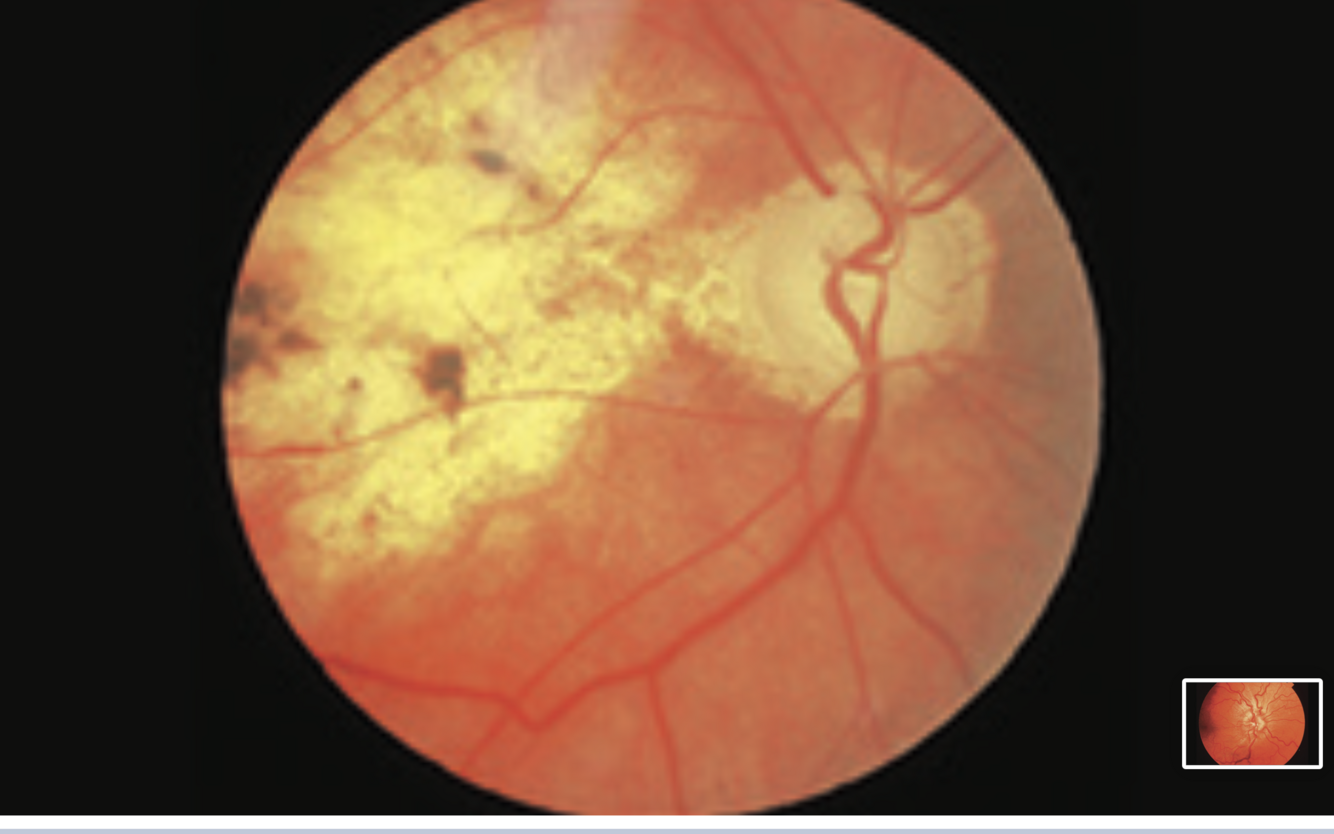

Advanced proliferative diabetic retinopathy

- hard exudates

-haemorrhages

-neovascularisation